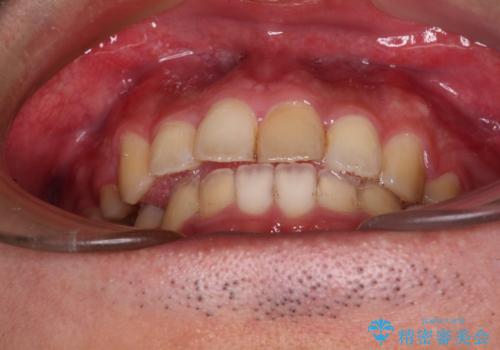

後戻りでデコボコの前歯 インビザライン矯正治療

下顎骨が左側に変位しているため、正中が合わないことは予想できましたが、歯列が整った後も咬み合わせが安定せず、咬み合わせを落ち着かせるために1年以上の期間を要しました。

噛みにくさの改善に時間がかかってしまうことがインビザラインの欠点の1つといえます。